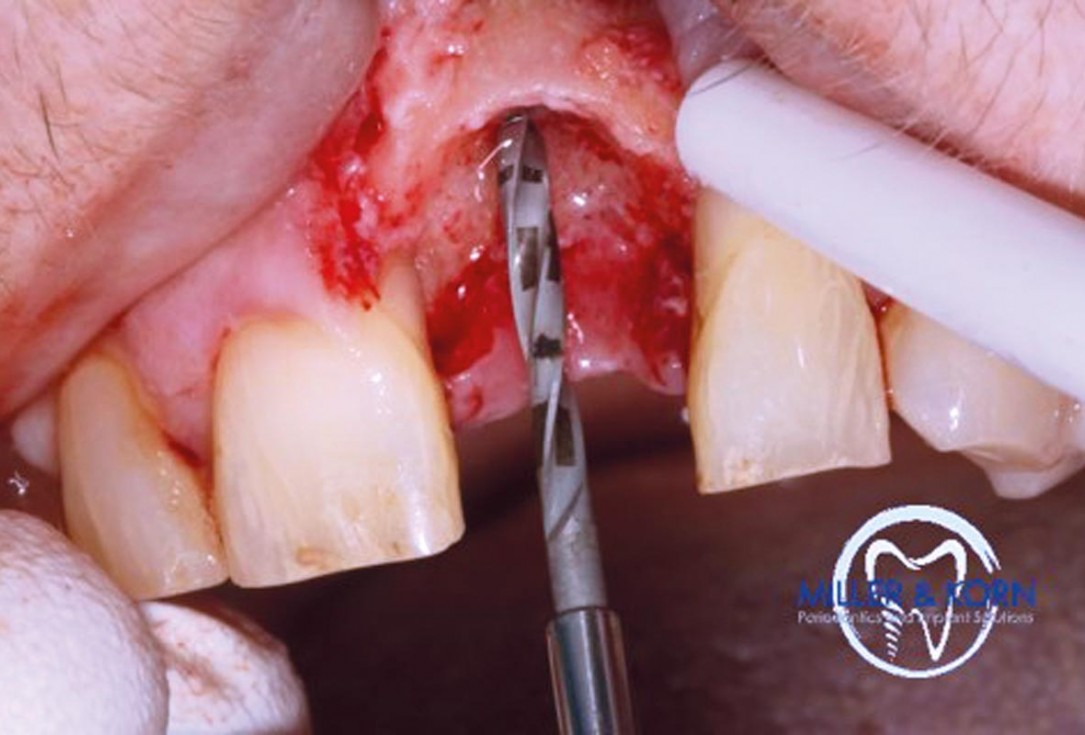

10/39 - Pilot drilling with a 2.2 mm twist drillImmediate implant placement and correction of horizontal and vertical bone loss using an allograft bone ring, cerabone® and Jason® membrane - Drs. Miller and Korn